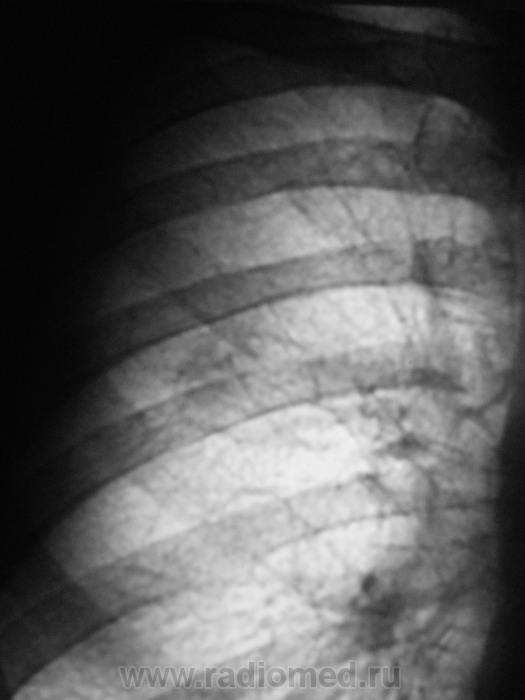

В плане дообследования был сделан стандарт.

Томограммы.

Когда производили боковую рентгенограмму лаборанты заметили, что пациент с трудом поднимает руку.

На свой страх и риск, лаборанты самостоятельно досняли плечевую кость.